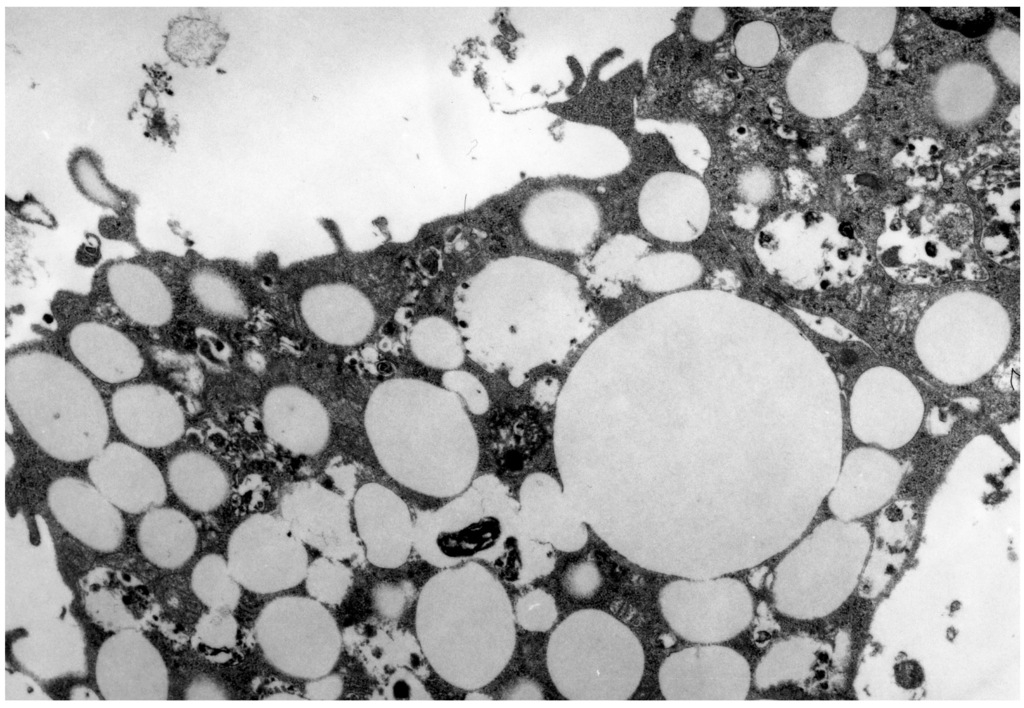

- Bobryshev, Y.V. Monocyte recruitment and foam cell formation in atherosclerosis. Micron 2006, 37, 208–222. [Google Scholar] [CrossRef]

- Tertov, V.V.; Orekhov, A.N. Metabolism of native and naturally occurring multiple modified low density lipoprotein in smooth muscle cells of human aortic intima. Exp. Mol. Pathol. 1997, 64, 127–145. [Google Scholar] [CrossRef]

- Tertov, V.V.; Sobenin, I.A.; Gabbasov, Z.A.; Popov, E.G.; Jaakkola, O.; Solakivi, T.; Nikkari, T.; Smirnov, V.N.; Orekhov, A.N. Multiple-modified desialylated low density lipoproteins that cause intracellular lipid accumulation. Isolation, fractionation and characterization. Lab. Investig. 1992, 67, 665–675. [Google Scholar]